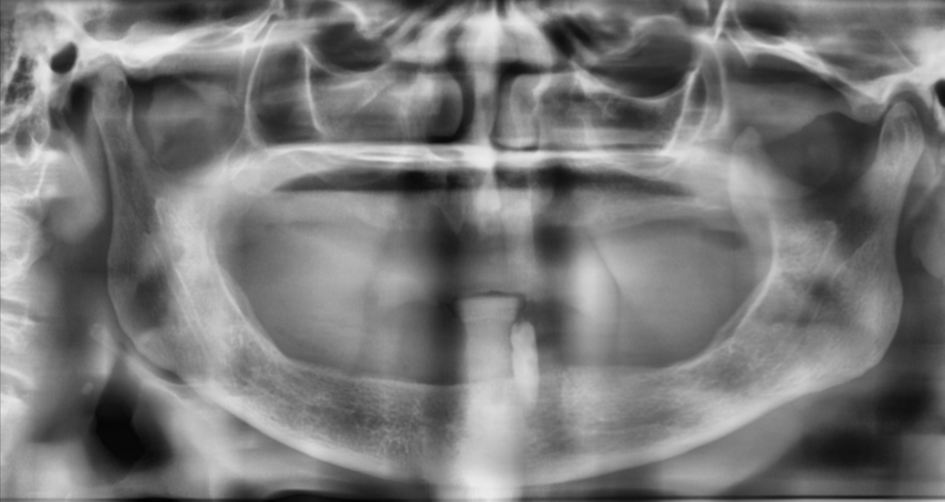

Figura 3 – Raio-X panorâmico inicial sem próteses removíveis em boca.

Para o planejamento da cirurgia guiada, foi necessária a duplicação da prótese da paciente em resina acrílica. A peça duplicada recebeu marcações com guta-percha para servir como referência radiográfica. Foram realizadas duas tomografias: uma com a prótese posicionada em boca e outra da prótese isoladamente, a fim de possibilitar a sobreposição das imagens e o planejamento virtual preciso da cirurgia.